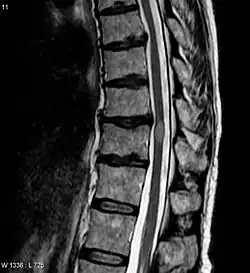

| Acute myelitis | intramedullary lesion > 3 contiguous segments, or spinal atrophy ≥ 3 contiguous segments |

A retrospective study found that prevalence of neuromyelitis optica spectrum disorders was 1.5% among a random sample of neurological patients, with a MS:NMOSD ratio of 42:7. Among 13 NMOSD patients, 77% had long spinal cord lesions, 38% had severe optic neuritis, and 23% had brain or brainstem lesions. Only 56% had clinically definite NMO at follow-up.[72]